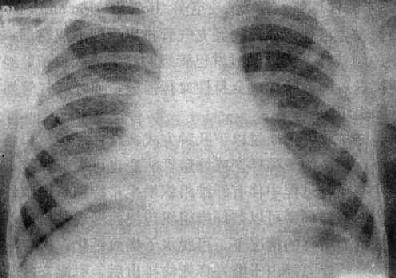

右肺结核球

图3-1-25 右肺结核球

右肺内带可见椭圆形致密影,轮廓光滑,内有斑状钙化